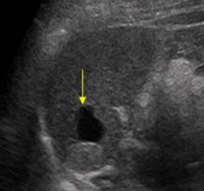

Identify this image.

Splenic cyst